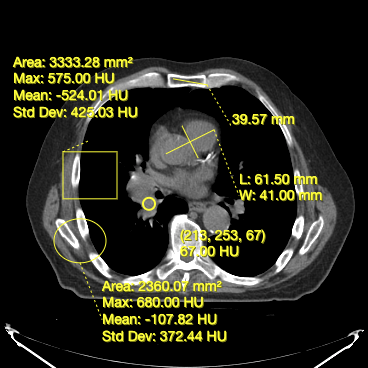

- Measuring width and length for a structure (Bidirectional Tool)

- Measuring area and statistics for a rectangular area (RectangleRoi Tool)

- Measuring volume and statistics for a ellipsoid (EllipseRoi Tool)

- Getting the underlying value for a voxel (Probe Tool)

Below, you can see a screenshot of the annotation tools that are available in Cornerstone3DTools.

Cornerstone3DTools is capable of calculating dynamic statistics based on the modality of the volume being rendered. For instance, for CT volumes a ProbeTool will give Hounsfield Units and for PET it will calculate SUV stats.